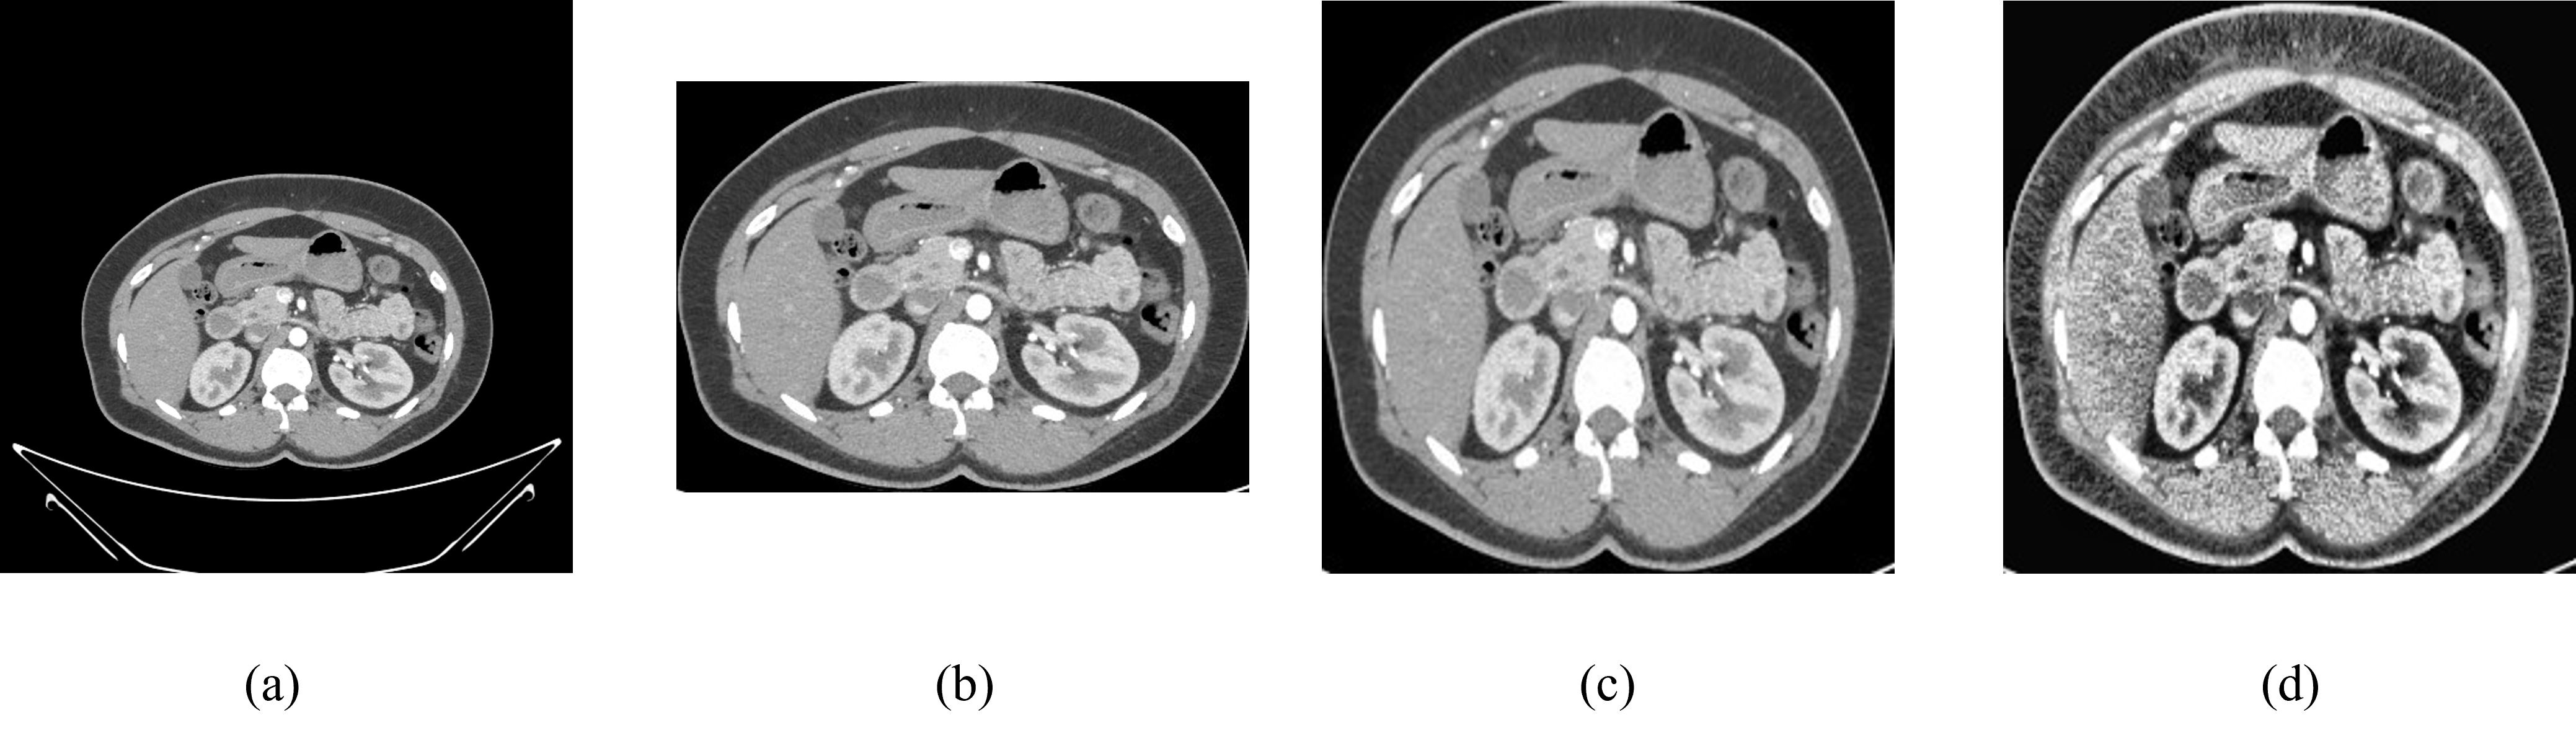

The initial phase of our image processing workflow involves meticulously cropping the CT scan images to isolate and emphasize the pertinent anatomical structures. This cropping process serves a dual purpose: first, it effectively eliminates extraneous background noise and non-essential elements from the images, thus enhancing the clarity and focus on the regions of interest. Second, it ensures that subsequent analyses are conducted with precision and efficiency, as they are directed toward the critical anatomical features essential for diagnosis and evaluation. Figure 3(a) is a raw dataset after that it has been cropped as shown in figure 3(b).

Following the cropping stage, we proceed to standardize the resolution of the images to a uniform size, typically resizing them into a standardized dimension of 224x224 pixels. This standardization is crucial for several reasons. Firstly, it facilitates consistency across the dataset, ensuring that all images are represented in a comparable format, which is essential for reliable and accurate analysis. Standardizing the resolution also helps to streamline subsequent computational processes, as it reduces variability and simplifies the integration of various image processing techniques and algorithms. Figure 3 (c) is an image after resizing it into 224x224 pixels.

5.1.2 Apply Contrast-Limited Adaptive Histogram Equalization (CLAHE) to the Data.

CALHE, or Contrast Adaptive Local Histogram Equalization, is an innovative technique that enhances image contrast by adjusting to local intensity variations, unlike traditional global histogram equalization methods. By considering the local context, CALHE proves particularly valuable for identifying subtle anatomical structures and anomalies in medical images. Its adaptive approach revolutionizes visualization, offering unprecedented precision and detail, thus advancing both research and clinical practice in radiology and beyond. Figure 3 (d) is an image after applying CLAHE which enhances the image more than regular raw data.

Figure 3: (a) Raw Normal Kidney Image (b) Cropped Image (c) Resized Image (d) CLAHE Applied Image